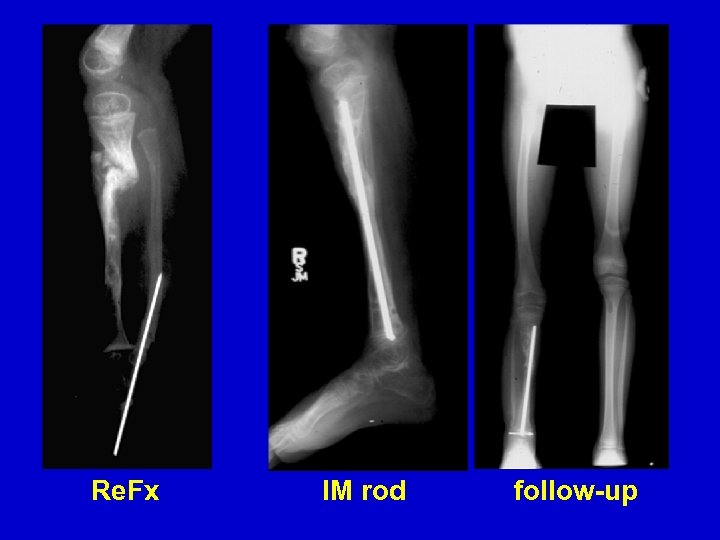

Type II Treatment Bone transport Acute shortening

Re. Fx IM rod follow-up